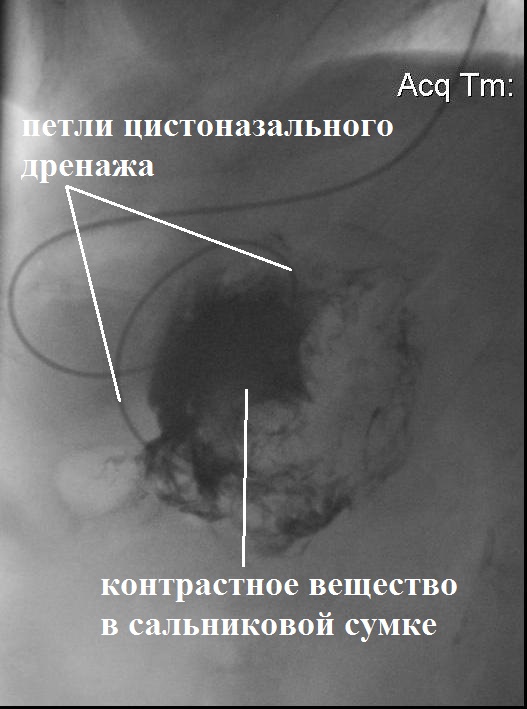

Для контроля функционирования установленных дренажей 06.10.2017 г. выполнена рентгенофистулография через цистоназальный дренаж. После неравномерного заполнения контрастом сальниковой сумки выявлено отсутствие контрастирования цистогастрального дренажа и поступления рентгеноконтрастного препарата в просвет желудка. Полученные данные свидетельствовали о неудовлетворительном дренировании ОЖС в связи с наличием в полости густого содержимого, секвестров и недостаточного диаметра цистогастрального дренажа (рис. 4).

Рис. 4. Фистулограмма на 2-е сут после цистоназального дренирования ОЖС сальниковой сумки (14-е сут болезни)